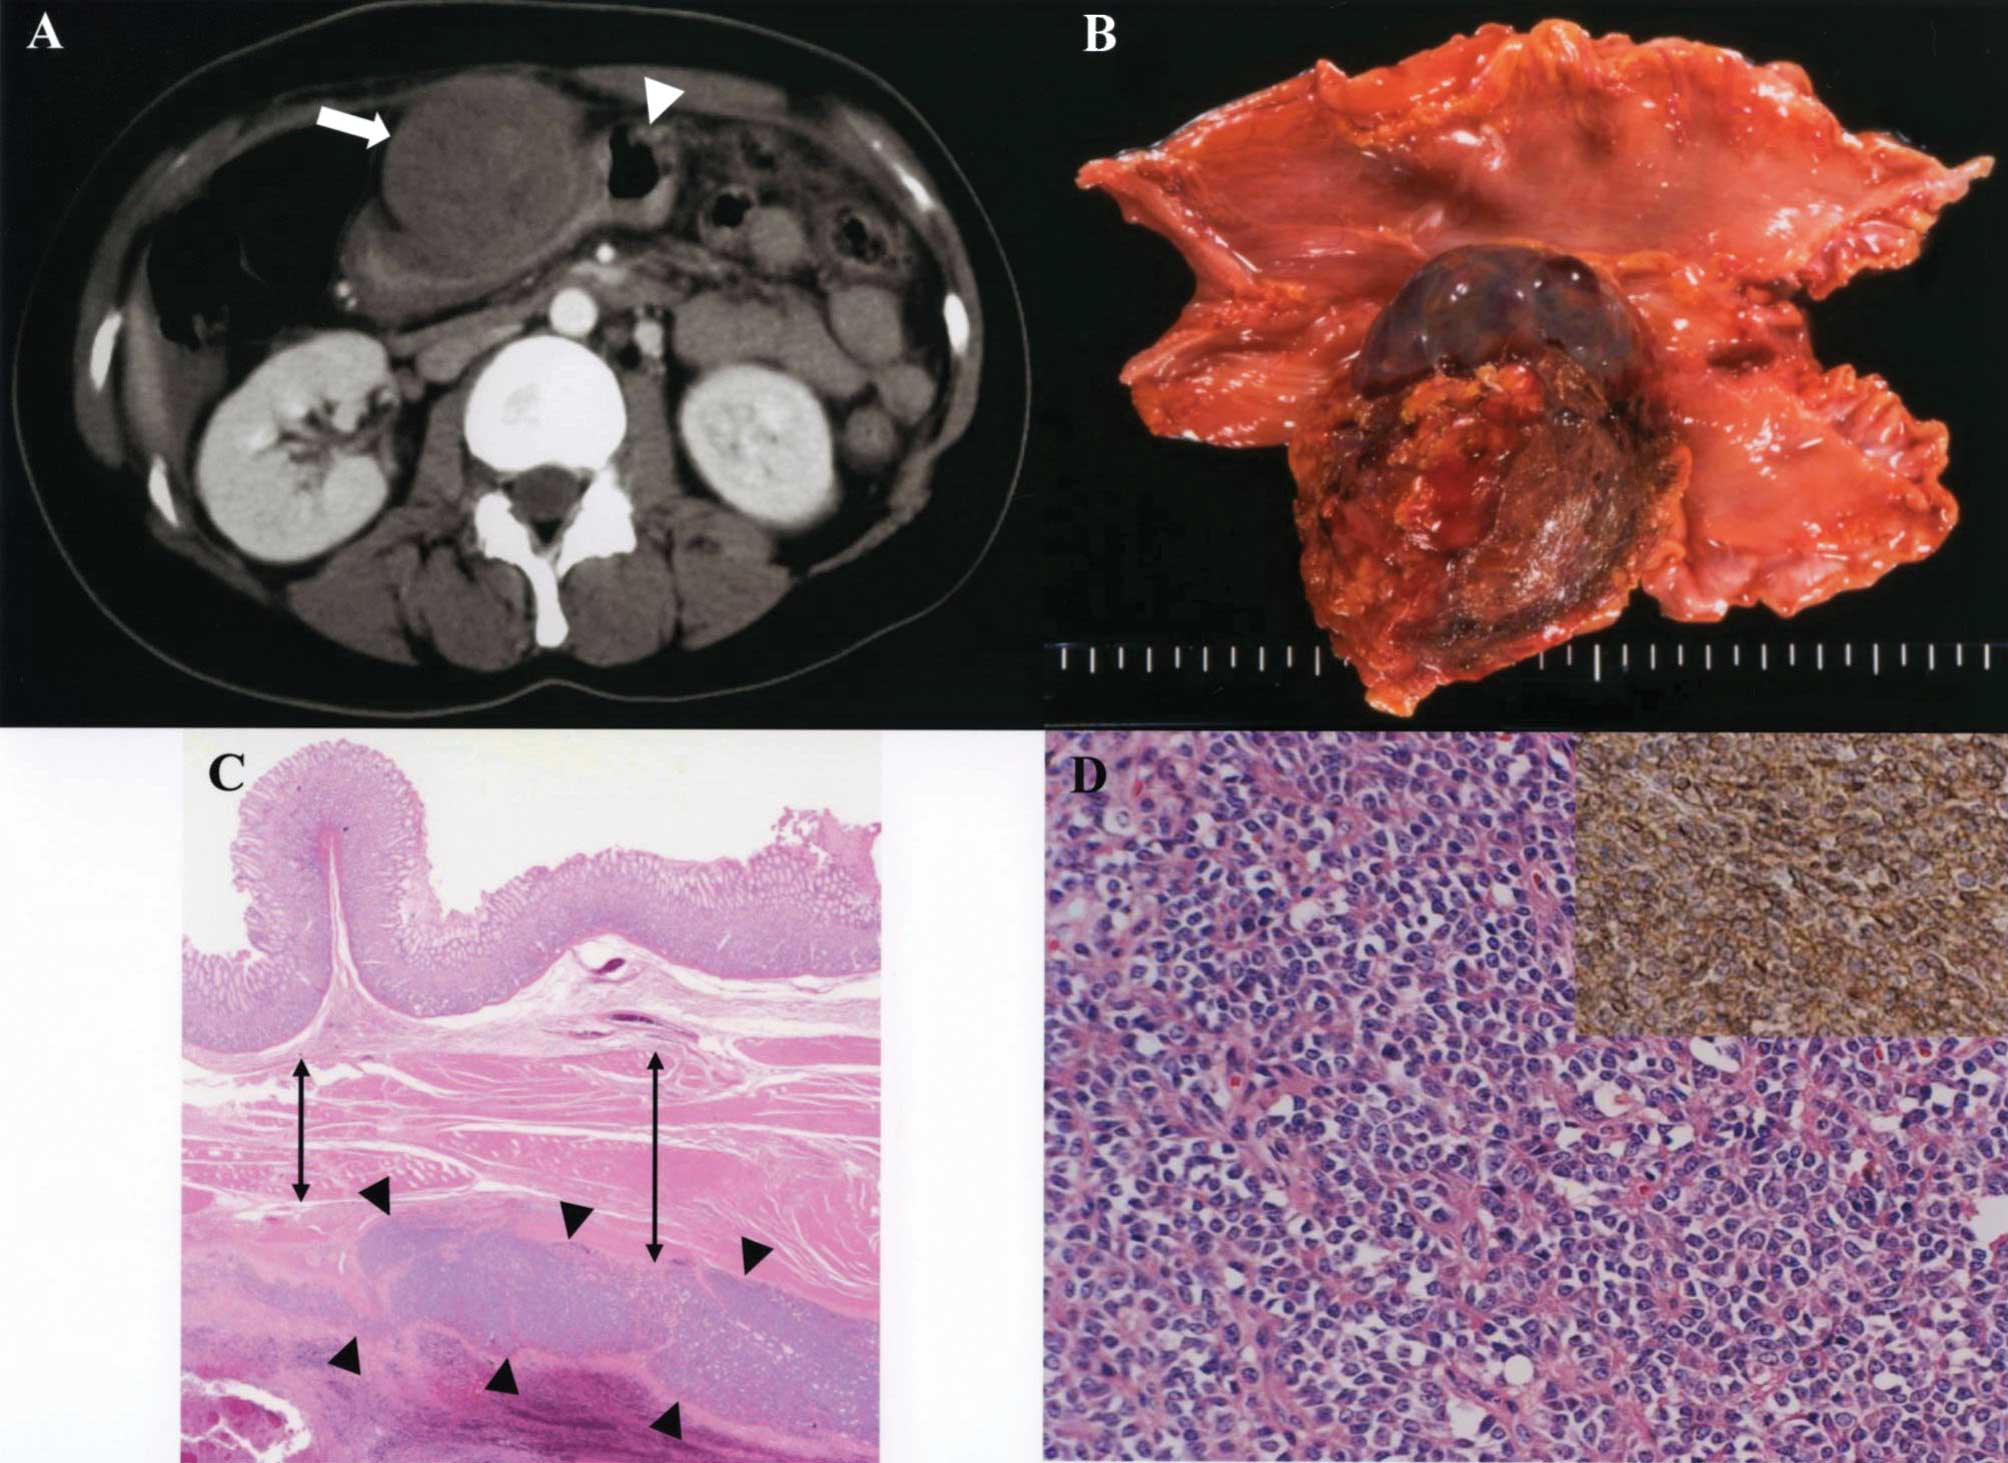

A 41-year-old Japanese woman was admitted with abdominal pain in 2000 to Saiseikai Niigata Second Hospital, Niigata, Japan. A contrast-enhanced computed tomography scan revealed a solid mass in the anterior wall of the stomach (Fig. 1A). She underwent a distal gastrectomy and regional lymphadenectomy. The resected specimen contained a firm, round tumor with extraluminal growth, 90×55 mm in diameter, located in the anterior wall of the stomach (Fig. 1B). Histological examination revealed the tumor arising from the muscularis externa of the stomach (Fig. 1C). Tumor cells were characterized by uniform, compact, round to oval nuclei, a modest amount of pale eosinophilic cytoplasm, and pseudorosette formation (Fig. 1D). Tumor cells showed positive immunoreactivity for CD99 (Fig. 1D), vimentin, CD117 (c-kit), S100, chromogranin A and synaptophysin. The chromosomal karyotype demonstrated the translocation t(11;22)(q24;q12) (Fig. 2). Molecular analysis using reverse transcription-polymerase chain reaction revealed the EWS-FLI1 fusion gene translocation t(11;22)(q24;q12). Thus, the primary gastric tumor was determined to be an ES/PNET.

Figure 1

(A) Contrast-enhanced computed tomography image showing a solid mass (arrow) arising from the stomach (arrowhead). (B) The resected specimen showing the solid round tumor with extraluminal growth, located in the anterior wall of the stomach. (C) Hematoxylin and eosin staining. The tumor (arrowheads) with extraluminal growth expanding from the gastric muscularis externa (double headed arrows) is shown. (Original magnification, ×10). (D) Hematoxylin and eosin staining. The tumor cells were characterized by uniform, compact, round to oval nuclei, a modest amount of pale eosinophilic cytoplasm and pseudorosette formation. Upper right inset indicates the positive immunoreactivity of tumor cells when stained with an anti-CD99 antibody. (Original magnification, ×400).